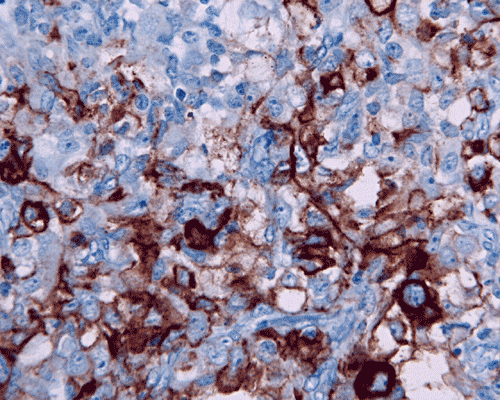

Immunohistochemistry, the defining diagnostic staining is loss of INI1 nuclear immunoreactivity in the tumor cells. The classic rhabdoid cells are also strongly and uniformly positive for vimentin. In fact, immunohistochemistry for vimentin is helpful in identifying rhabdoid cells. Other than vimentin, a long list of antigens is variably detected in rhabdoid tumors reflecting the polyphenotypic nature of these tumors. Epithelial membrane antigen (EMA) is detected in the rhabdoid cells and epithelial components. About half of the cases are positive for smooth muscle actin. Expression of these two antigens are rather unusual for other tumors of the central nervous system. S-100 protein is variably detectable among different cases. Intermediate filaments including neurofilament, glial fibrillary filaments, and cytokeratin are detectable in many cases. Synaptophysin is detectable particularly when a medulloblastoma-like component is present. Placental alkaline phosphatase (PLAP) and beta-human chorionic gonadotrophin (hCG) are not detectable but alpha fetal protein (αFP) can be demonstrated in some cases [Rorke LB et al., 1996; Burger PC et al., 1996].

Biallelic inactivation of the SMARCB1 gene (INI1/hSNF5) located in chromosome 22q11.2, either by homozygous deletion or having one mutant allele and the other allele with deletion or mitotic recombination, accounts for majority of molecular alterations seen in AT/RT [Rorke LB et al., 1996; Biegel JA et al., 1992, Rorke LB et al., 1995; Biegel JA et al., 1999; Biegel et al., 2002; Taylor MD et al., 2000]. Such deletion is also detected in other malignant tumors such as epithelioid sarcoma and renal medullary carcinoma. Detection of 22q11.2 deletion by interphase fluorescence in situ hybridization (FISH) would be a helpful aid to establish a diagnosis [Bruch LA et al., 2000]. Very rarely, mutation or inactivation of the SMARCA (BRG1) gene which also belongs to the SWI/SNF pathway can be seen in AT/RT. Molecular confirmation can be done using sequencing (such as next generation sequencing), FISH and chromosomal microarray analysis.